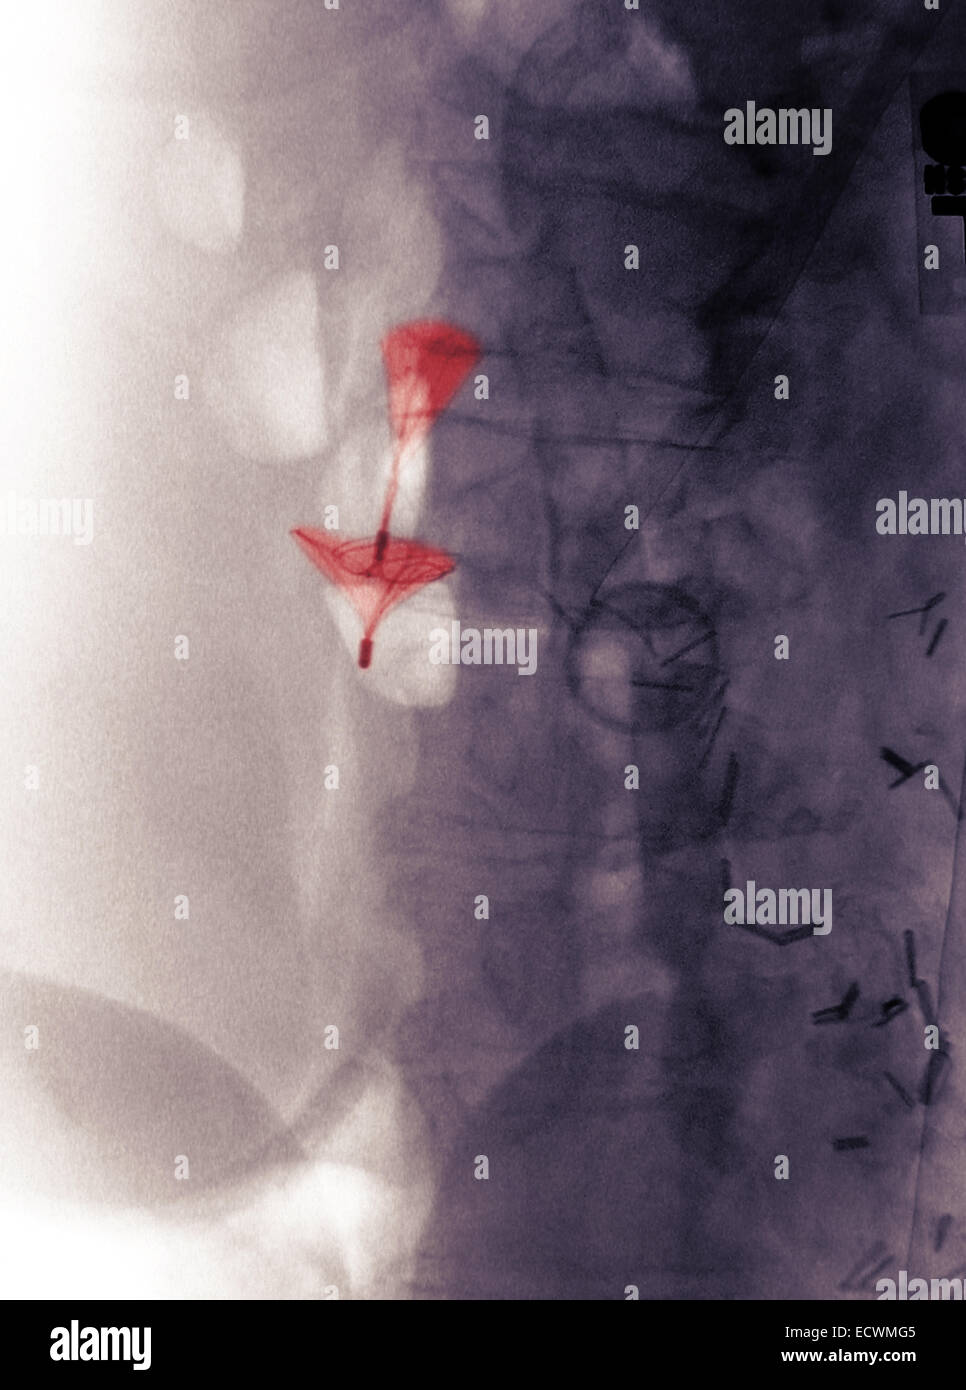

From www.alamy.com

abdomen xray showing a vena cava blood clot filter Stock Photo Alamy Blood Clot Filter An ivc filter is a device that can stop blood clots from going up into the lungs. A vena cava filter is a small metal device that stops blood clots from traveling to your lungs (pulmonary embolism). Others have an ivc filter placed to get them ready for a surgery. What is an ivc filter? Learn about the different types. Blood Clot Filter.

abdomen xray showing a vena cava blood clot filter Stock Photo Alamy Blood Clot Filter Ivc filters can help prevent pes and save your life. An ivc filter is a device that can stop blood clots from going up into the lungs. What is an ivc filter? Find out how they work, when they are needed, and what are the possible complications and alternatives. A vena cava filter is a small metal device that stops. Blood Clot Filter.

abdomen xray showing a vena cava blood clot filter Stock Photo Alamy Blood Clot Filter Others have an ivc filter placed to get them ready for a surgery. An inferior vena cava (ivc) filter is a device designed to block blood clots in a vein — usually in the leg — from migrating to the lung. A vena cava filter is a small metal device that stops blood clots from traveling to your lungs (pulmonary. Blood Clot Filter.

abdomen xray showing a vena cava blood clot filter Stock Photo Alamy Blood Clot Filter Learn about the reasons, risks, and preparation for this surgery. An ivc filter is a device that can stop blood clots from going up into the lungs. A vena cava filter is a small metal device that stops blood clots from traveling to your lungs (pulmonary embolism). Find out how they work, when they are needed, and what are the. Blood Clot Filter.